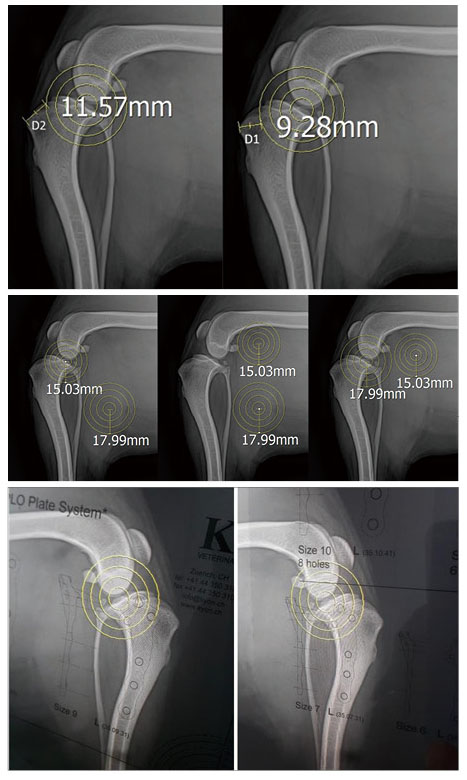

■ TPLO Plan - TPA 5˚ 맞추기

• TPA를 측정한다.

• 적절한 saw blade size를 결정한다.

• 적절한 osteotomy 위치를 결정한다.

• 필요한 tibial plateau rotation의 정도를 결정한다(Preoperative TPA chart 참고).

• 안전하고 적절한 plate size를 결정한다.